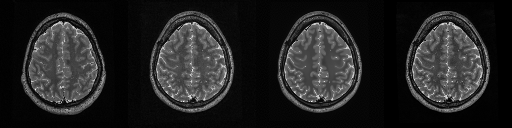

HCP T2w dataset

We utilize images from the publicly available Human Connectome Project (HCP) [51] T2-weighted (T2w) images dataset for the task of compressed sensing, which contains brain images from 47 patients. The HCP dataset includes cross-sectional images of the brain taken at different levels and angles.

Compressed sensing

We train a flow-based model from scratch on 10,000 randomly sampled images, utilizing the ncsnpp architecture [9] with minor adaptations for grayscale images. We employ compression rates , meaning . The measurement operator is given by a subsampled Fourier matrix, whose sign patterns are randomly selected. We evaluate our reconstruction algorithm’s performance on 200 randomly sampled test images.

We present the quantitative and qualitative results of compressed sensing in Tab. 1 and Fig. 4, respectively. As shown in Tab. 1, our method consistently achieves the best performance across varying compression rates . In Fig. 4, our method produces reconstructions that are more faithful to the original images, with fewer artifacts, leading to higher accuracy and clearer details.